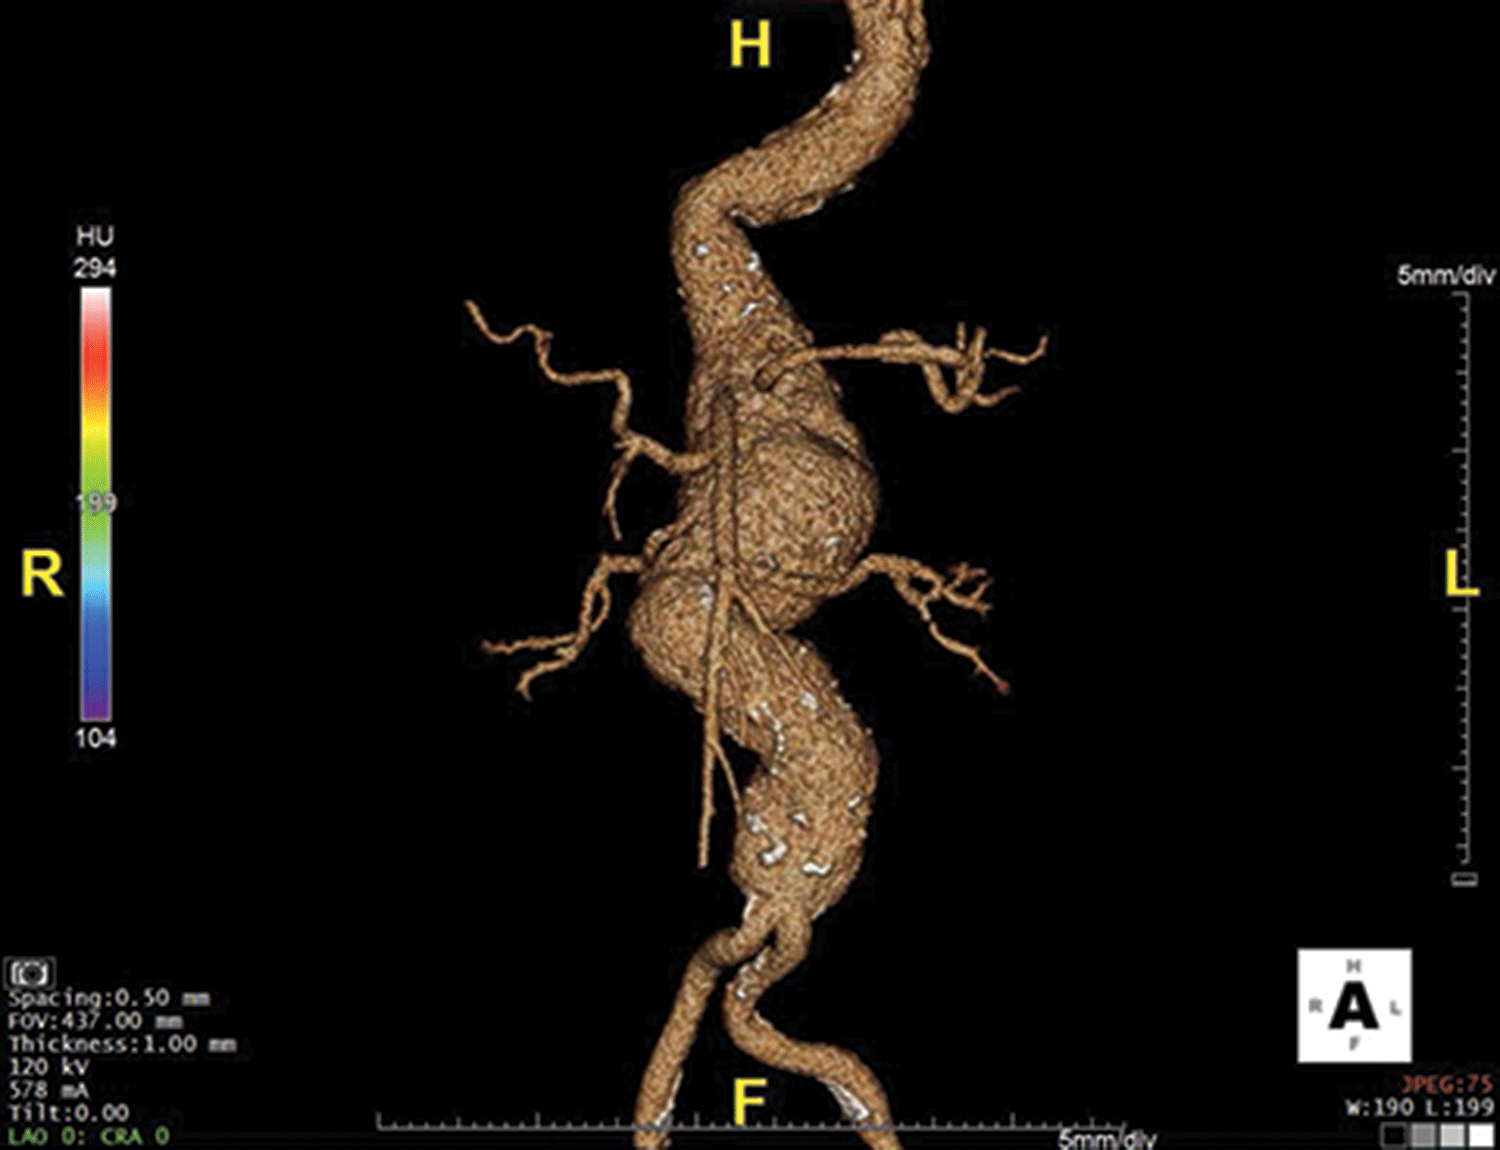

Gastrointestinal Stromal Tumors of the Small Intestine

- GIST is a genetically heterogeneous disease caused by mutations in KIT (70 to 80%), PDGFR, the RAS pathway (K-ras, H-ras, N-ras, BRAF, NF1), SDH A to Dsubunits, FGFR1, and ETV6-NTRK3, among others.

- Cytoreductive surgery in selected patients with metastatic GIST has comparable outcomes to second-line systemic therapy.